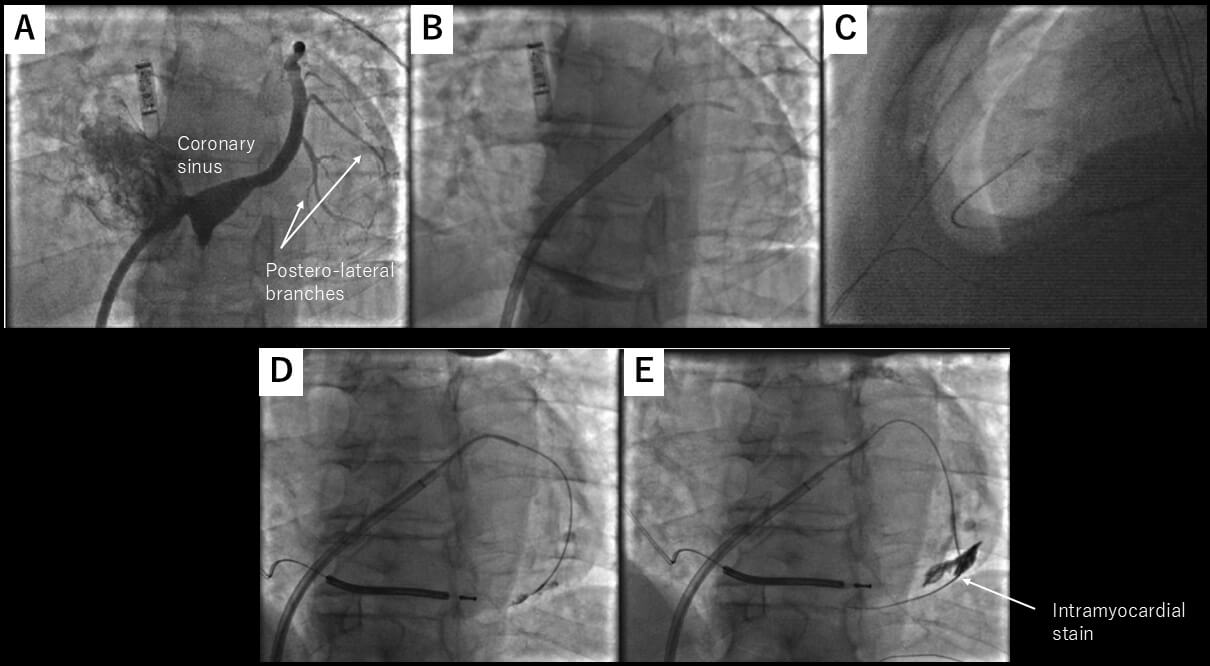

Although several techniques have been implemented to minimize the risk of inadvertent injury to the heart or adjacent structures, such as the needle-in-needle approach [13, 14] or the use of sustained apnea with RV angiography, [16] we still encounter a fundamental challenge: typically, there is minimal or no anatomical separation between the parietal and visceral pericardium at the time of needle entry. To overcome this issue, the use of CO2 insufflation into the pericardial space was first introduced by Greenbaum et al. [17]. The rationale behind the use of CO2 is that it is non-flammable, colorless, highly soluble in blood, and rapidly absorbed by tissues, making it an ideal gas for transient anatomical separation. CO2 rises anteriorly in the pericardial space when a patient is in the supine position, providing a temporary air gap between the anterior RV and the pericardium, aiding the operator in confirming adequate separation of the visceral and parietal pericardium by fluoroscopy. Greenbaum et al. [17] used the right atrial appendage (RAA) as an exit to the epicardial space with the back end of a stiff coronary guidewire to perforate the RAA, which was limited by a high failure rate due to the inability to effectively perforate the thick RAA myocardium. Therefore, as first described by Silberbauer et al. [18], this was later modified to perforate the distal end of the coronary venous branch as an exit to the pericardial space. A high-tip-load coronary guidewire (0.014-inch) is used to perforate a distal lateral or anterolateral coronary vein branch supported by a deflectable sheath inserted in the coronary sinus. A microcatheter is advanced into the pericardial space over this wire once a coronary guidewire is in the epicardial space. Then, after a small contrast injection into the pericardial space, CO2 is manually insufflated into the pericardial space. This allows for precise subxiphoid access with a 22G microneedle (which later replaced the initially used 18G Tuohy needle to avoid rapid gas loss and pericardial collapse) (Fig. 6A–C, Ref. [18]). Severe hemopericardium is usually rare, as verified by the Epi-CO2 registry [19], as opposed to the conventional “dry” puncture approach, which reported RV puncture in 3–17% and significant pericardial bleeding in up to 9% of cases. The safety is further confirmed in a single high-volume referral center [8] as well as a mid-volume referral center [20].

Fig. 6.

CO2 insufflation from the coronary sinus exit. (A) Left anterior oblique view of the coronary sinus. The target vein is one of the lateral veins, as highlighted by the arrows. (B) One of the lateral veins was selected by diagnostic JR4 catheter, and microcatheter was advanced over a coronary guidewire. (C) Microneedle entered the pericardial space, which has been insufflated with CO2. (D,E) Coronary wire may stray into an intracardiac vein. These figures were modified from the original figure of Silberbauer et al. [18].

This technique is also useful for detecting pre-existing pericardial adhesion by injecting contrast once pericardial access is obtained by a microcatheter, as described in the Epi-CO2 registry [19]. Also, on a case report basis, this technique was reported to be effective in patients with epicardial adhesion [10]. However, there is still insufficient evidence for the use of this technique for severe epicardial adhesion.

One important thing to be aware of when using a coronary sinus as an exit is that a coronary wire may stray into an intracardiac vein, as described in the initial report (Fig. 6D,E) [18]. Also, the risk of dislodging the coronary sinus lead for cardiac resynchronization therapy with a defibrillator (CRT-D) needs to be taken into account due to the complexity of the maneuver in the coronary sinus.